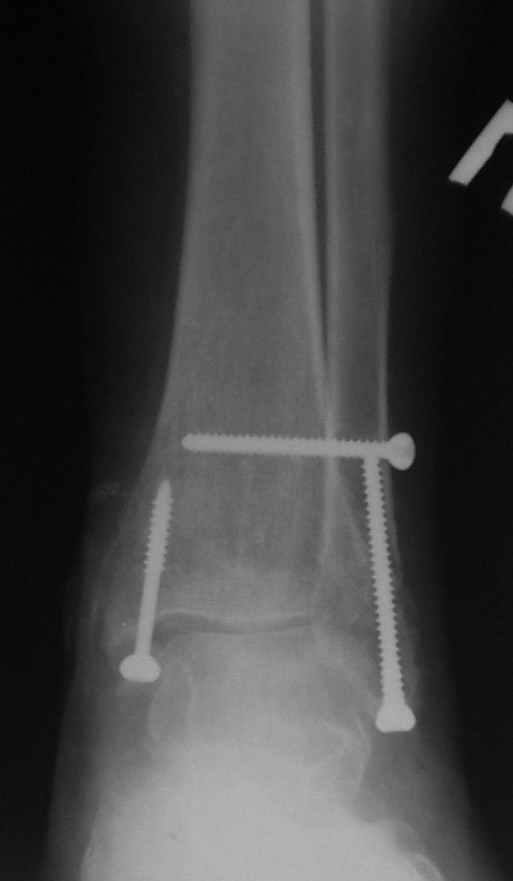

Ниже рентгенограммы

Операция 29 июля

Риторический вопрос - в каком руководстве рекомендован такой способ остеосинтеза наружной лодыжки?

Очевидно, такой результат операции был запрограммирован. При невосстановленной длине и практически нефиксированной малоберцовой кости (этот кортикальный винт - как карандаш в стакане), при неустраненном подвывихе, невправленной и тоже нефиксированной внутренней лодыжке нет стабильной вилки сустава. Если такую операцию сделать даже сразу, а не через 4 месяца, то результат ожидаем

тот же.

Ну а уж если выбран остеосинтез - нначать надо было с репозиции малоберцовой кости с точным восстановлением длины, с фиксацией треть-трубчатой пластиной по задней поверхности. Позиционный винт

избыточен - повреждение практически подсиндесмозное. А если бы

действительно было повреждение синдесмоза - в 4 месяца позиционный винт - не решение. Внутренню лодыжку такую - надо было бы спицами и проволочной петлей. Извините за эти банальности.